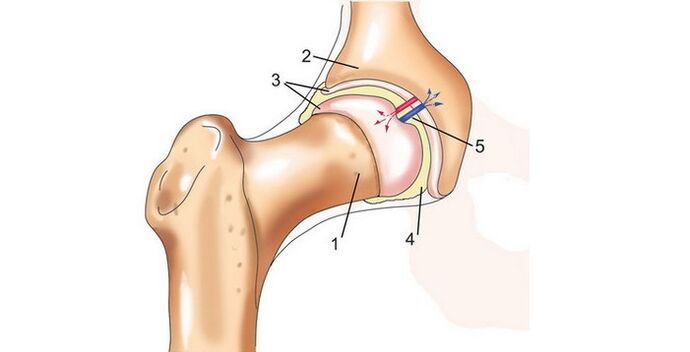

A csípőízület a csípőcsont és a combcsont között helyezkedik el. Ezért a gyulladást és a patológiát a sacroiliacalis ízületek csípőízületének arthrosisának nevezik.

A köztük lévő tér magában foglalja a szinoviális membránt és a hialin porcot is, ezek az összetevők együttesen biztosítják az ízület normál működését. Mindez jól látható a csípőízület arthrosisának fotóján.

A hialinporc munkája a szivacs munkájához hasonlít. Amikor összehúzódik, az ízület terhelésétől függően a szükséges mennyiségű folyadékot bocsátja ki, amely kenő hatású. A terhelés leállása után a porc pórusai újra megtelnek folyadékkal. Egy olyan betegség kialakulásának egyik oka, mint a csípőízületi arthrosis, az ízületi folyadék tulajdonságainak megváltozása.